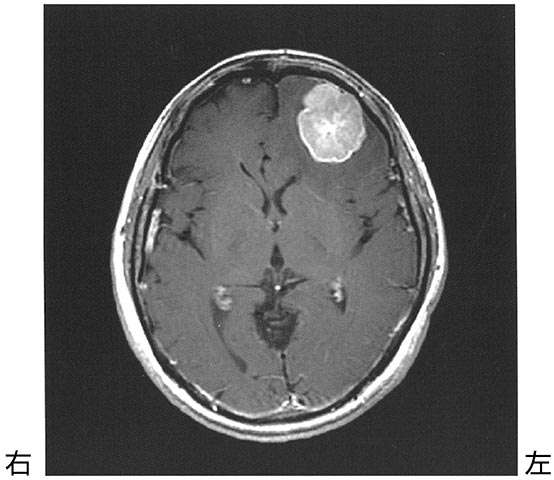

52歳の女性.起床時の頭痛と嘔気を主訴に脳神経外科を受診した.頭部造影MRI T1強調像を下に示す.頭蓋内腫瘍摘出術が予定されており,術前より理学療法が依頼された.神経症候として認める可能性が最も

- 1.失 語

- 2.拮抗失行

- 3.情緒障害

- 4.注意障害

- 5.遂行機能障害

解答: 2